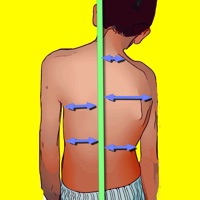

1. Back surface topography by means of structured light in the screening is not needed to mark the necessary points for calculating the Potsi Index.

2. The Potsi App calculates the Potsi Index according to the above mentioned developed topographic method (Suzuki N, Inami ) and offers a way to evaluate external back deformities with noninvasive technique.

3. POTSI Index is very sensitive in revealing any frontal plane asymmetry and could help identify moderate deformities which might otherwise be missed in clinics or physical examination.

5. Posterior Trunk Symmetry Index (POTSI) is a useful Index in the assessment of spinal deformity.

7. The Potsi Index is the sum two variables Height Asymmetry Index (HAI) and Frontal Asymmetry Index (FAI).

8. Height asymmetry indexes are obtained as the sum of height differences of the shoulders, axillary folds, and waist creases, and it is normalized with the division of its value by the vertical distance from the C7 vertebra to the baseline of the gluteal cleft.